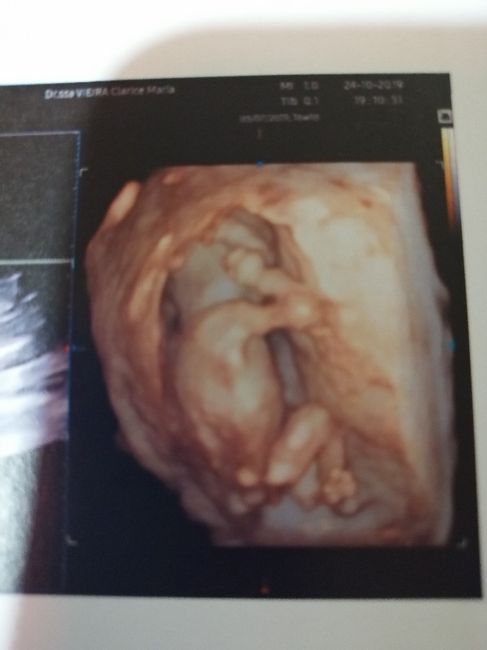

Mamme di Aprile 2020Da Mara , Il 25 Ottobre 2019 alle 07:59

Buongiorno a tutte! Ho scoperto venerdì il mio positivo...oggi sono a 4+4 e la mia dpp è il 3 aprile 2020. Mi sa che sono la prima! Sono emozionatissima! Adesso aspetto...